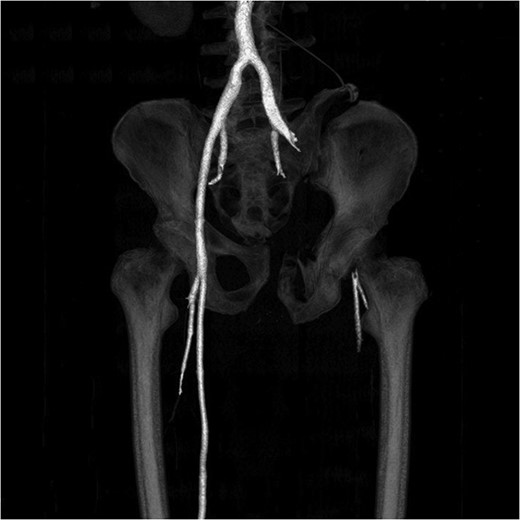

A 55-year-old male arrived at the ER, a large tree having fallen across his pelvis. The patient was hypotensive at the scene. He received over 1500 ml of crystalloid in route to the emergency room. Upon arrival to St. Mary’s Medical Center, the patient had a systolic pressure of 70. His heart rate was in the 130 s. The patient was awake and alert. A left subclavian central line was placed and he was transfused with two units of O-blood. The patient’s abdomen was soft and nontender. The patient had blood at his meatus. The patient’s pelvis was tender to palpation. His left leg was cold, mottled and pulseless. There was no femoral pulse on the left side. The chest x-ray was normal, however, the pelvis film revealed extreme widening and displacement of the symphysis pubis (Fig. 1). A bedsheet was wrapped around the patient’s pelvis and another two units of O-packed red blood cells were administered. Additionally, he was given four units of fresh frozen plasma. The patient was started on norepinephrine to control his persistent hypotension. His systolic blood pressure rose into the mid-90s and the patient was taken to the CT scanner. The CT scan revealed that the patient had an acute occlusion of his left iliac artery, as well as a large left iliac wing fracture with a massive associated hematoma. A right iliac wing fracture was located near the sacroiliac joint. There was pubic diastasis, as well as a left superior rami fracture with a modest associated hematoma. There was no extravasation of dye (Figs 2 and 3). The patient was taken directly to the operating room because he was developing significant abdominal distention in the face of continued hypotension. Anesthesiologists placed a second large-bore central line for fluid resuscitation. An exploratory laparotomy was performed, revealing an intraperitoneal bladder rupture. The patient was bleeding freely from his pelvic hematoma. Multiple attempts were made to pack the pelvis tightly with laparotomy pads, but efforts were unsuccessful. Because of the distorted anatomy obtaining proximal and distal control of the iliacs was extremely difficult. The patient suffered massive retroperitoneal venous bleeding, which we were unable to control. The patient exsanguinated on the operating room table; despite having received over 30 units of packed red blood cells, 30 units of fresh frozen plasma, several 10 packs of platelets, cryoprecipitate and factor VII A.

Large retroperitoneal hematoma. Arrow depicts injured left iliac artery.